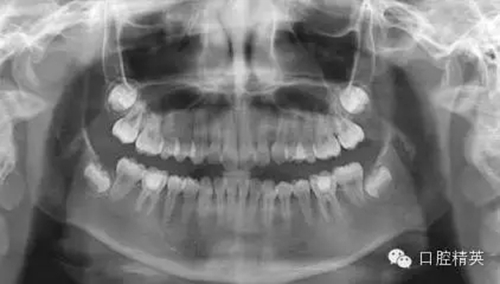

1,術(shù)前X-ray,常規(guī)術(shù)前攝片,為患者和自己保留一份客觀記錄。